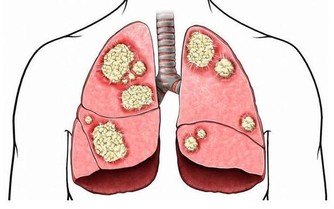

事實上,脂肪肝會導致更嚴重並且常常是致命的肝臟疾病,包括肝癌。肝病的主要階段包括單純性脂肪肝(脂肪變性)、纖維化和最嚴重的階段,也就是肝硬化,它可以導致肝功能衰竭和肝癌。